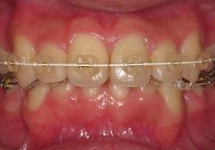

☆審美ワイヤー(光拡散型)の使用例と

ホワイトワイヤー(コーティング)での治療例

審美ホワイトワイヤー

光拡散ロジウムコートtypeワイヤー

ゴールドシリーズ審美ワイヤー

ホワイトコーティングtypeワイヤー